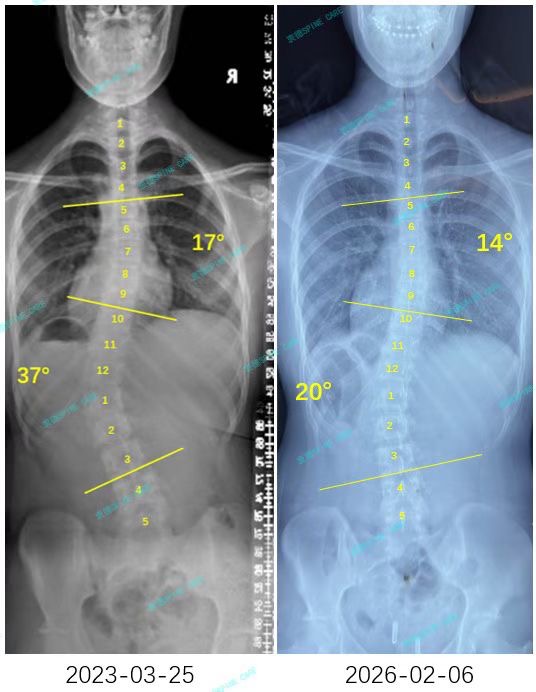

我是小欣,今年15岁,一次普通的校园体检,让我第一次听到了"脊柱侧弯"这个词。X光片上那道刺眼的曲线显示:腰弯37度,胸弯17度。镜子前,我清楚地看见自己扭曲的肩膀和歪斜的骨盆,连最简单的站立都变得不再自然,心里满是自卑与无助。

I'm Xiaoxin, and I'm 15 years old. During a routine school physical examination, I first encountered the term "scoliosis." The glaring curve on the X-ray revealed that my lumbar spine was at a 37-degree angle, while my thoracic spine was at a 17-degree angle. In front of the mirror, I could clearly see the distorted shoulders and tilted pelvis, and even the simplest act of standing became unnatural, leaving me with feelings of inferiority and helplessness.

结果出来,腰弯从37度降到20度,胸弯从17度降到14度,腰椎旋转也降到4度!看着片子上变化,泪水一下涌出来,这三年的汗水没白流。那张对比X光片,记录的不只是角度的变化,更是一个少女重获自信的历程。

The results showed that the curvature of the waist had decreased from 37 degrees to 20 degrees, the curvature of the chest had decreased from 17 degrees to 14 degrees, and the rotation of the lumbar spine had also decreased to within 5 degrees!As I looked at the changes on the X-ray, tears welled up in my eyes; all the hard work over the past three years had not been in vain. That X-ray comparison not only documented the changes in the angles but also the journey of a young girl regaining her confidence.